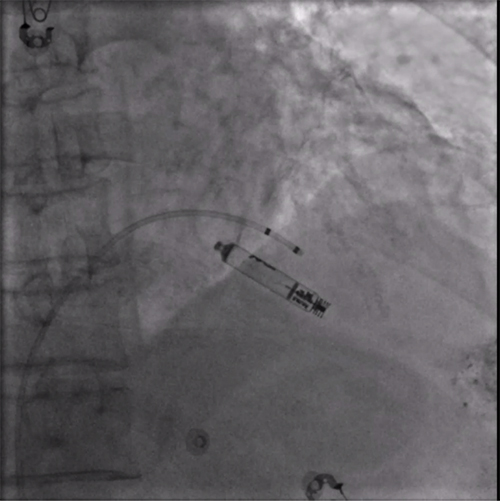

经过周密的术前准备,彭晖、孙志军两位主任带领邸北冰主治医师、柳晓娜主治医师和梁立丰医师在内的起搏电生理团队,于心脏介入手术室为患者实施手术。手术团队股静脉穿刺成功后,首先对下腔静脉进行造影并将外鞘放置送入下腔静脉,随后将新型主动固定螺旋无导线起搏器顺利跨瓣送入右心室目标位置,旋入前测试无导线起搏器各项电学参数良好,确认位置合适后旋入固定起搏器,在植入过程中动态测试起搏器各项参数以辅助判断固定程度,达到标准后进入对接栓模式,再次测试起搏器固定位置稳定、各项参数良好后释放起搏器,最后撤出鞘管,顺利完成手术。整个手术流程高效有序,医疗团队成员紧密配合,默契无间,仅耗时40分钟共同完成了这一具有挑战性的任务。

RAO造影确认位置安全

LAO造影确认指向间隔部

电学标测参数良好,在此旋入1.5圈后进入对接栓模式,

摇摆与电学参数测试后释放起搏器

植入后右前斜

植入后左前斜